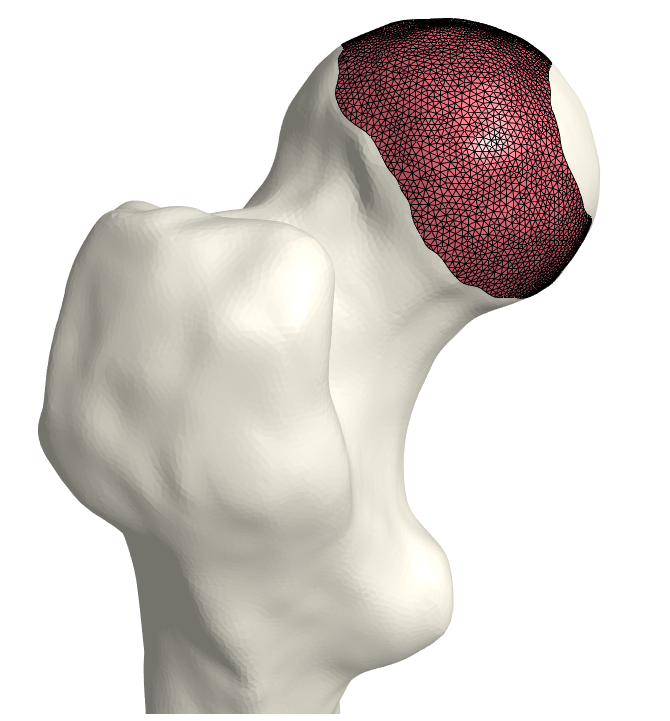

That is, we extrude each vertex 𝐯jsubscript𝐯𝑗\mathbf{v}_{j} in the direction of its normal by the displacement wjsubscript𝑤𝑗w_{j}. As a final step, we invert the bone-attached face normals before collecting the three disjoint sets of faces and vertices into a single mesh, (𝒱C,C)subscript𝒱𝐶subscript𝐶(\mathcal{V}_{C},\mathcal{F}_{C}). Observe in Fig. 3 the cartilage sub-surfaces combined into a single mesh.

Refer to caption

(a) Femoral cartilage.

(b) Femoral cartilage.

(c) Pelvic cartilage.

Figure 3: The final cartilage generated by our method for a femur (a), (b) and a pelvis (c). Notice how the cartilage aligns with the anatomical lines.